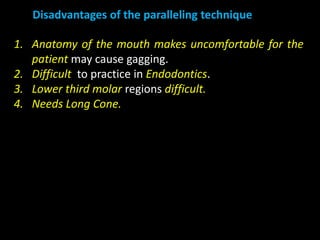

2. The paralleling cone technique provides accurate images with little magnification and no superimposition but is more difficult for patients. The bisecting angle technique is easier for patients but results in more image distortion.

3. Special considerations for intra-oral radiography include techniques for mandibular third molars, gagging patients, endodontic procedures, edentulous ridges, and pediatric patients.